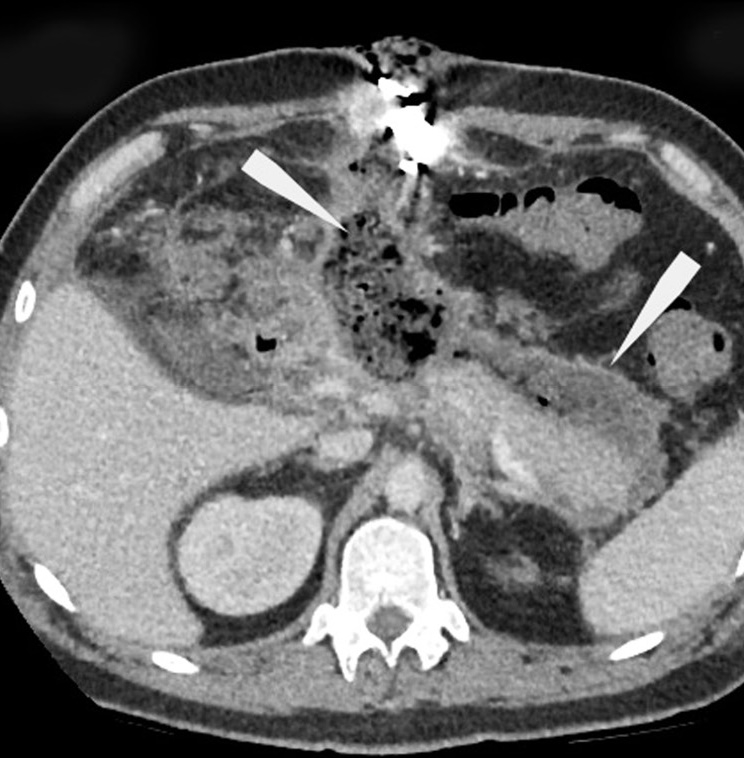

This study presents a rare clinical case of encapsulated necrotic pancreatitis, which was a complication of acute pancreatitis that arose against the background of alimentary disorders. The aspects of the semiotics of radiation diagnostic methods in the follow-up control of these pathologies were presented.

This case is notable for the manifestation of diseases upon hospital admission, as in the classical edematous form of acute pancreatitis, with a further increase in negative dynamics. This demonstrated the possible stepwise disease development, accompanied by a series of follow-up computed tomography between the clinical and morphological phases of acute pancreatitis and before the formation of pancreatic necrosis, which was complicated by sequestration of the pancreatic body with peripancreatic abscess formation. Afterward, the therapeutic paradigm was changed, and the place of the conservative approach was taken by active surgical tactics, followed by repeated manipulations and follow-up computed tomography and magnetic resonance until the improvement of the patient’s condition.